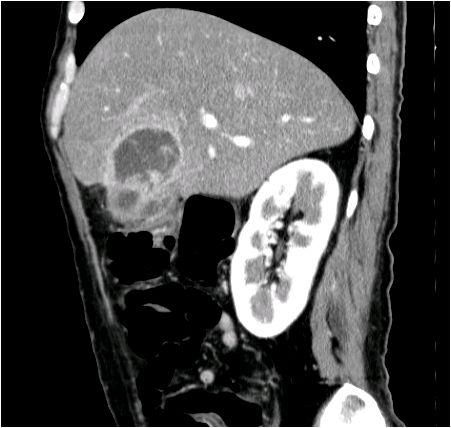

[黄色肉芽腫胆嚢炎] 手術:胆嚢摘出術(結腸切除術併施)

血液検査にて炎症反応の上昇を認め、精査の結果、急性胆嚢炎と診断。胆嚢摘出術(結腸切除術併施)を施行した。病理結果は黄色肉芽腫胆嚢炎であった。

CT画像